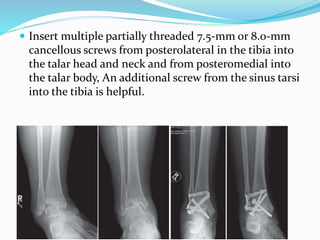

 Insert multiple partially threaded 7.5-mm or 8.0-mm

cancellous screws from posterolateral in the tibia into

the talar head and neck and from posteromedial into

the talar body, An additional screw from the sinus tarsi

into the tibia is helpful.